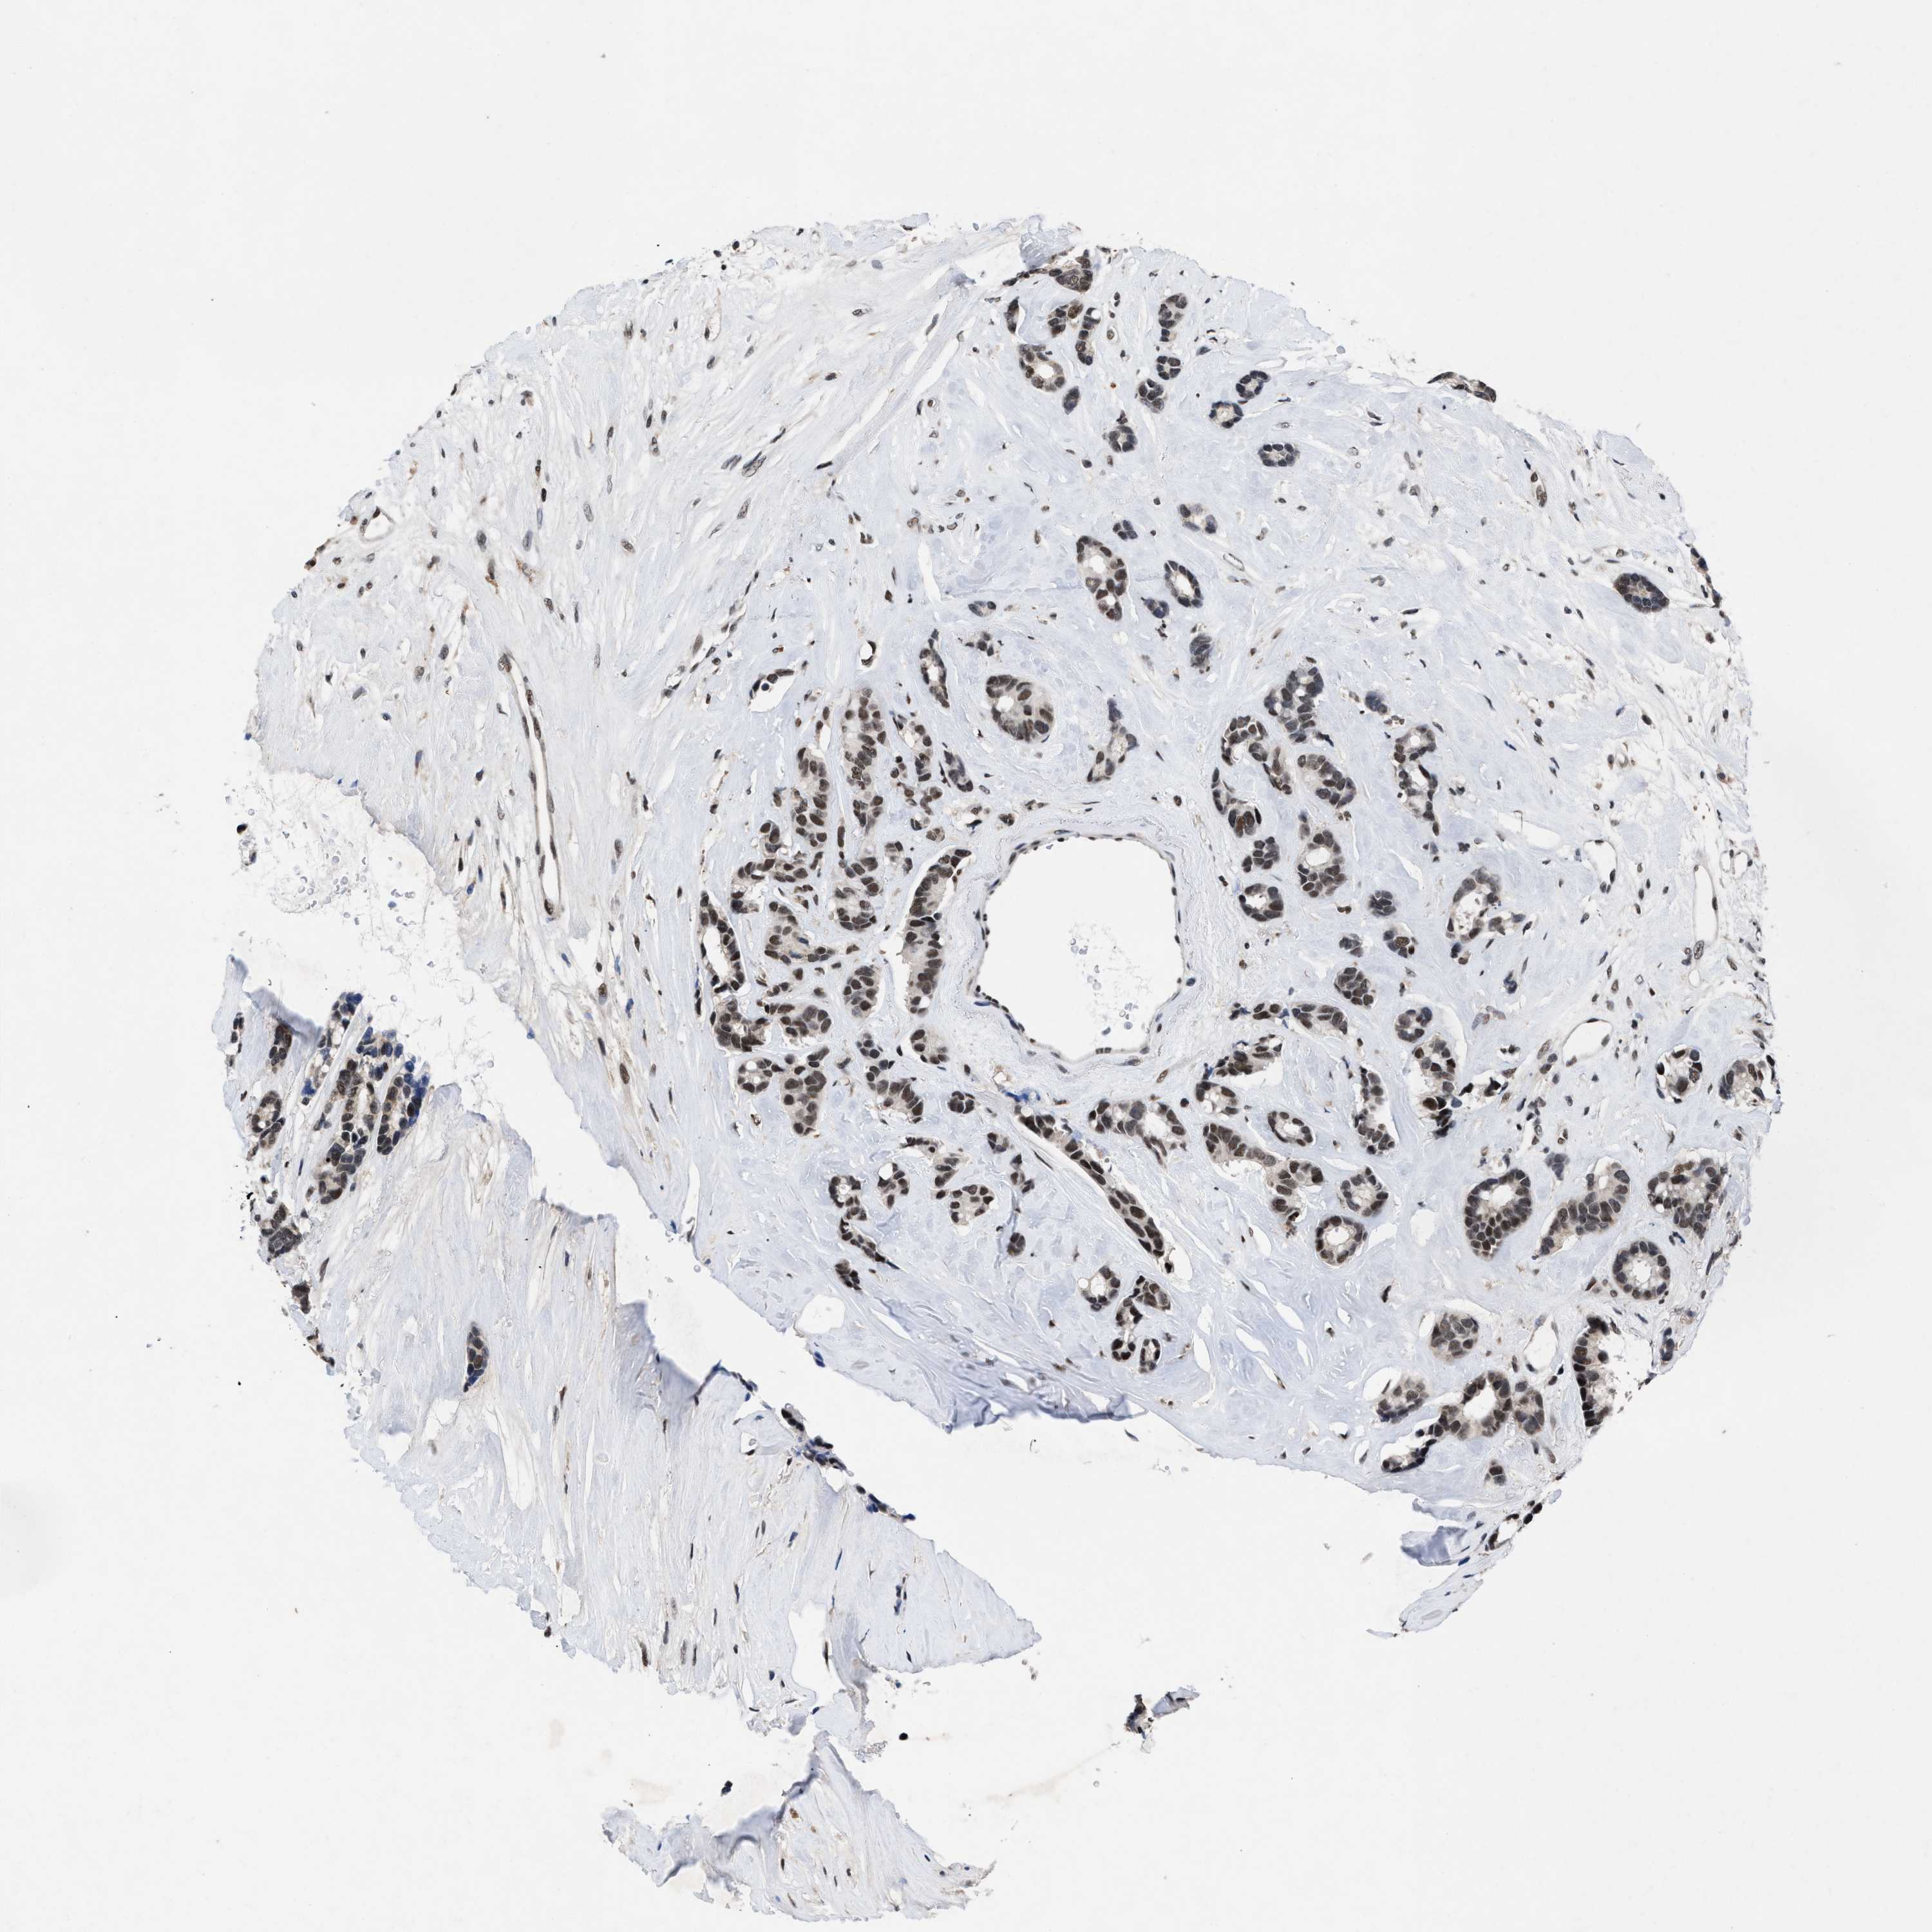

BRCA TCGA BRCA VALIDATION PROTEIN EXPRESSION